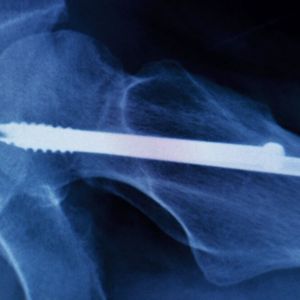

Konstruktion Die Top-10-Artikel für Konstrukteure

Ob Sensorik, Werkstoffe oder Textilien: Ganz unterschiedliche Komponenten tragen zum Erfolg eines innovativen Medizinprodukts bei. Lesen Sie nachfolgend die Top-10-Artikel aus dem ersten Halbjahr 2019, an denen kein Konstrukteur vorbeikommt.